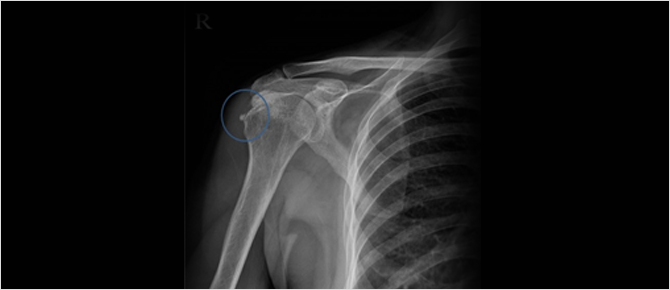

Calcific Tendonitis X-ray

Calcific tendonitis can be diagnosed through X-ray imaging, which reveals the calcifications formed in the tendon.